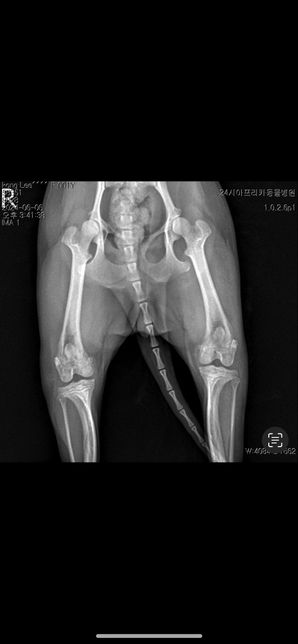

- 반려동물 건강반려동물Q. 강아지 십자인대파열 수술된게 엑스레이상으로 확인되나요?(수술후)양쪽슬개골이랑 한쪽 십자인대돌아갔다해서 수술 한 상태인데 다른동물병원에서는 이 사진을 보고 십자인대를 한줄 모르더라구요 엑스레이상으로는 확인이 안되나요?십자인대 수술 된건가요?..(수술전)